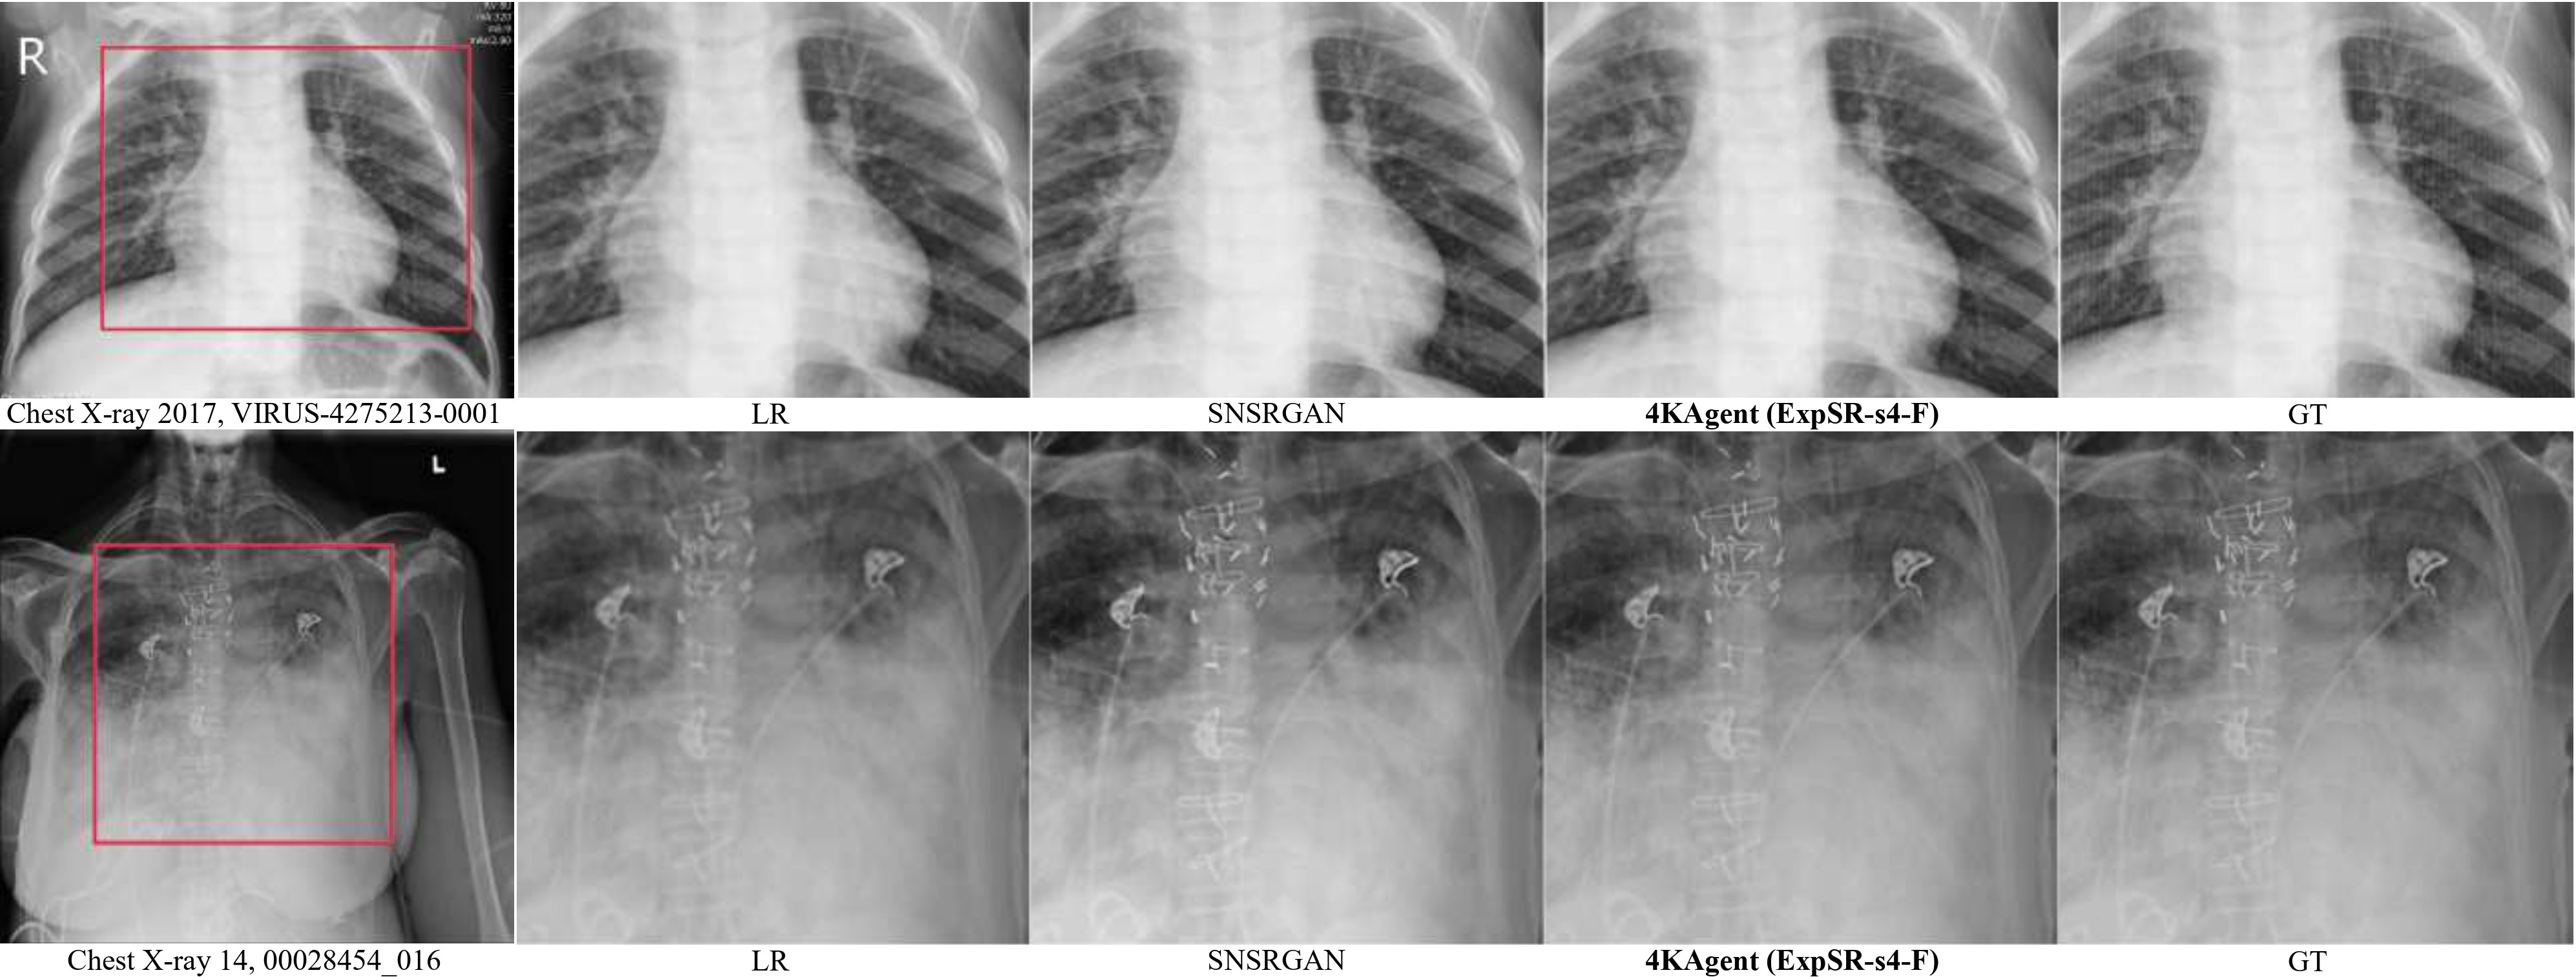

| Chest X-ray 2017 kermany2018identifying | 624 | |

| Chest X-ray 14 wang2017chestx | 880 | |